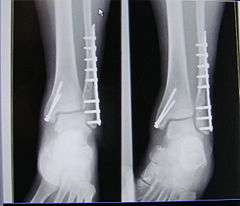

A trimalleolar fracture is a fracture of the ankle that involves the lateral malleolus, the medial malleolus, and the distal posterior aspect of the tibia, which can be termed the posterior malleolus. The trauma is sometimes accompanied by ligament damage and dislocation.[1]

Surgical repair utilizing open reduction and internal fixation is generally required, and because there is no lateral restraint of the foot, the ankle cannot bear any weight while the bone knits. This typically takes six weeks in an otherwise healthy person but can take as much as twelve weeks. Non-surgical treatment may sometimes be considered in cases where the patient has significant health problems or where the risk of surgery may be too great.[1]